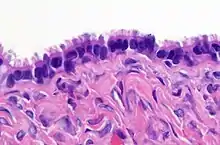

High magnification micrograph of a Brenner tumor, a type of surface epithelial-stromal tumor. H&E stain.

Brenner tumor

Brenner tumors are uncommon surface-epithelial stromal cell tumors in which the epithelial cell (which defines these tumors) is a transitional cell. These are similar in appearance to bladder epithelia. The tumors may be very small to very large, and may be solid or cystic. Histologically, the tumor consists of nests of the aforementioned transitional cells within surrounding tissue that resembles normal ovary. Brenner tumors may be benign or malignant, depending on whether the tumor cells invade the surrounding tissue.